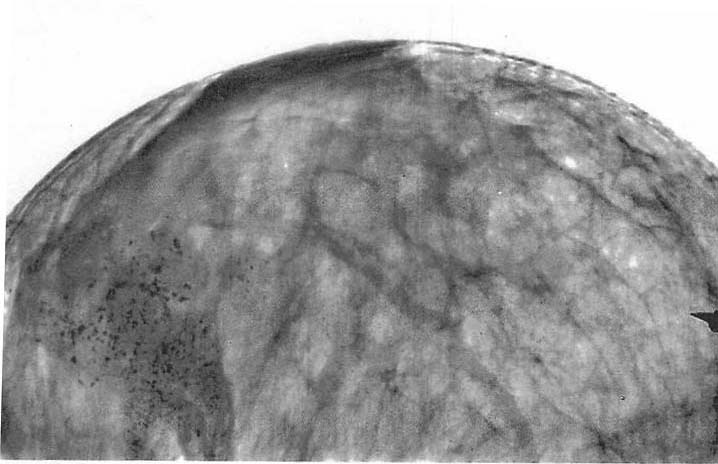

図4.画面下半の濃度の高い部分が腫瘍.正常部分に見られる細い索状陰影が失われている.

【要旨・解説】臨床例に初めて乳腺撮影を行なったライプツィヒ大学の,当時としては最も豊富な臨床例をもとに,乳腺疾患のX線診断について詳述した論文である.撮影法は側面像(ML撮影)のみであるが,腋窩を含みリンパ節転移も評価できるとしている.

1913年にベルリン大学のSalomonが発表した切除標本のX線撮影所見をもとに,病理学的背景を推測している.正常乳腺では,結合組織、中隔構造による弧状の索状陰影が認められ,乳癌では腫瘤陰影とともにこの正常索状陰影が失われ,不整な,ときに数珠玉状の索状陰影がみられるとしている(図4).鑑別として,びまん性嚢胞性慢性乳腺炎(現在でいう乳腺症)をあげている.石灰化に関する記載はない.びまん性病変よりも結節状病変の方が診断が難しいとしている点は興味深い.

圧迫が行なわれていないこともあり,供覧されている写真の画質は,現在から見ると著しく劣るが,本文の解説との対応も不明の点が多く,当時の苦労が偲ばれる.診断の基本は臨床所見であり,ま線所見はまだ補助的なものに過ぎないが,今後の発展に期待すると結んでいる.